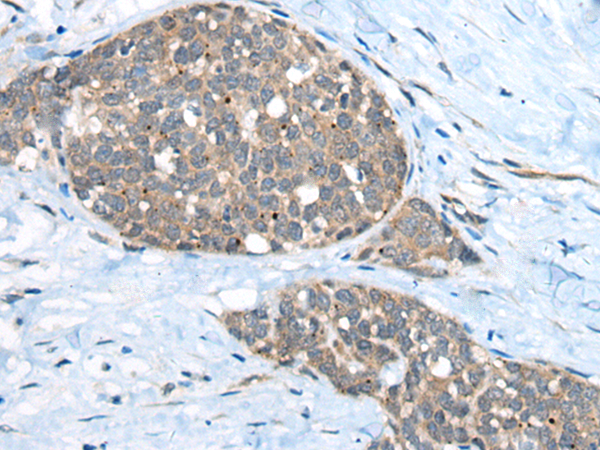

IHC positive control:

Human liver cancer

IHC Recommend dilution:

40-200